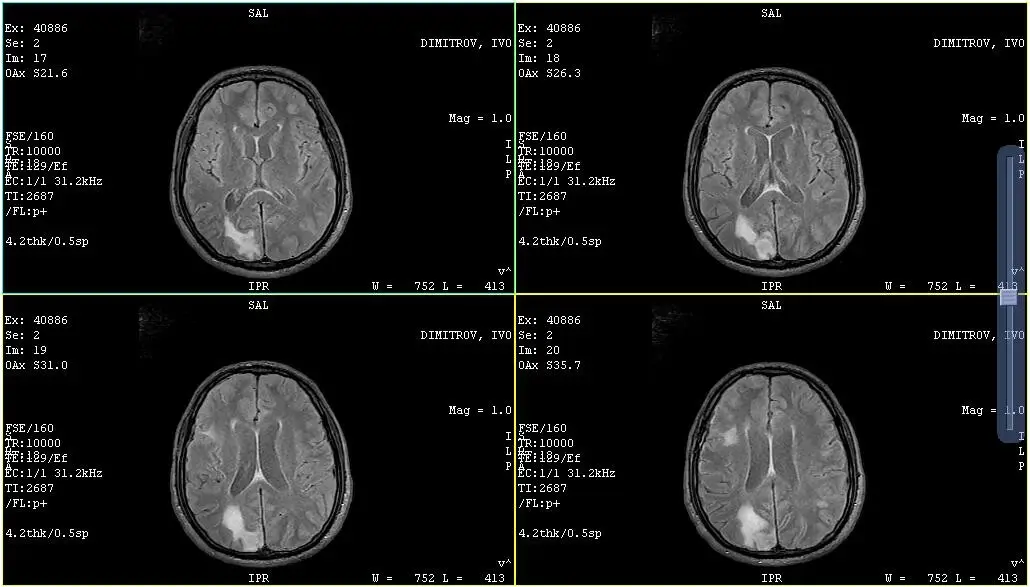

Само дни преди най-светлите семейни празници, стана ясно, че отново трябва да пътуваме за Турция! Откакто се прибрахме в България през юни, Иво е на имуномодулираща терапия (Леналидомид) и след края на курса, трябваше да се направи контролно ЯМР. На 16-ти декември направихме ЯМР-то в Аджибадем Сити Клиник Варна и за огромно съжаление резултатите показват рецидив на болестта и две нови огнища в задната част на мозъка. След като изпратихме диска с изследването на лекуващите лекари в Турция, те поискаха на 27-ми декември да сме там, за да направят ПЕТ скенер и други изследвания, на базата на които да преценят как да променят протокола за лечението. Така на 26-ти декември пътуваме за Истанбул, с огромна вяра и надежда, че лекарите там ще намерят най-доброто решение и лимфома на Иво отново ще бъде овладян. Коледа е времето на чудесата, а вие вече ни накрахте да вярваме, че те съществуват, така че отново се надяваме на нашето коледно чудо!

Just days before the brightest family holidays, it became clear that we have to travel to Turkey again! Ivo has been on immunomodulatory therapy (Lenalidomide) since we got back to Bulgaria in June and after the end of the course, we had to have a follow-up MRI. On the 16th of December we did the MRI in Ajibadem City Clinic Varna and unfortunately the results showed a relapse of the disease and two new foci in the back of the brain. After we sent the CD with the study to the treating doctors in Turkey, they requested that we be there on the 27th of December to do a PET scan and other tests based on which they could decide how to change the treatment protocol. So on the 26th of December we travel to Istanbul, with great faith and hope that the doctors there will find the best solution and Ivo's lymphoma will be controlled again. Christmas is the time of miracles, and you've already made us believe they exist, so here's hoping for our Christmas miracle again!